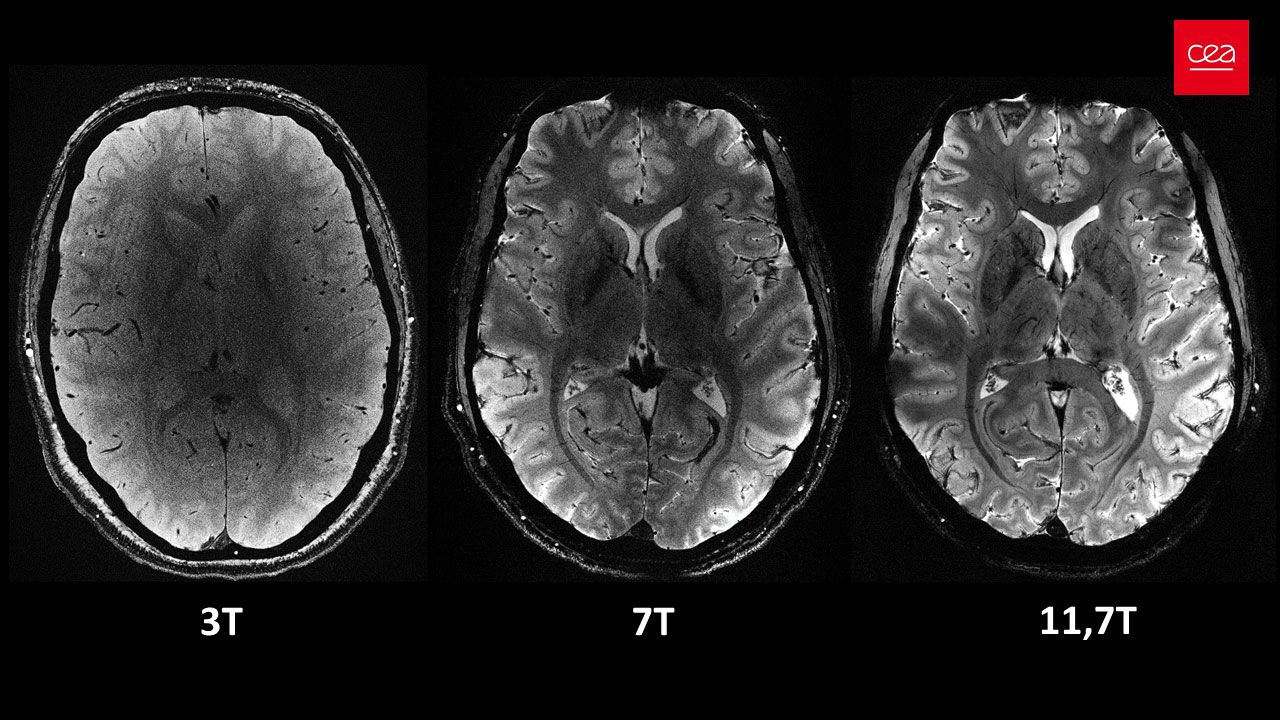

MRT-Aufnahme des Gehirns mit derselben Auflösung bei unterschiedlichen Magnetfeldstärken. Bei 3 Tesla und bei 7 Tesla sind Präzision und Schärfe geringer. Bei 11,7 Tesla liefert der Scan mehr Signale und größere Kontraste zwischen biologischen Geweben, was eine detailliertere Untersuchung des Gehirns ermöglicht.

Axial view of the human brain, with the same acquisition time but different magnetic field strengths.